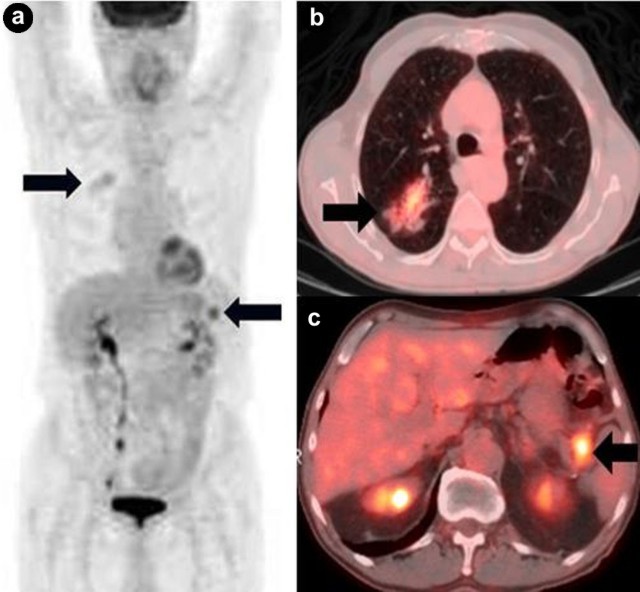

b) Pancreatic Metastasis from Lung Cancer

According to an autopsy study of patients with pancreatic tumors, lung cancer is the leading malignancy (18%) that disseminates to the pancreas [9]. Small cell lung cancer has the tendency to metastasize to the pancreas more frequently than non-small cell lung cancer. At the present time, almost all PET/CT data on lung cancer come from non-small cell lung cancer studies; only a few small cell lung cancer studies suggest that PET/CT has the potential to simplify and maybe improve the accuracy of the current staging system of small cell lung cancer (Figure 10).

|

Figure 10. a. Coronal PET maximum intensity projection image shows a prominent pancreatic metastasis from right lung small cell lung cancer (arrows). b. Coronal fused PET/CT image reveals the corresponding lesion. |